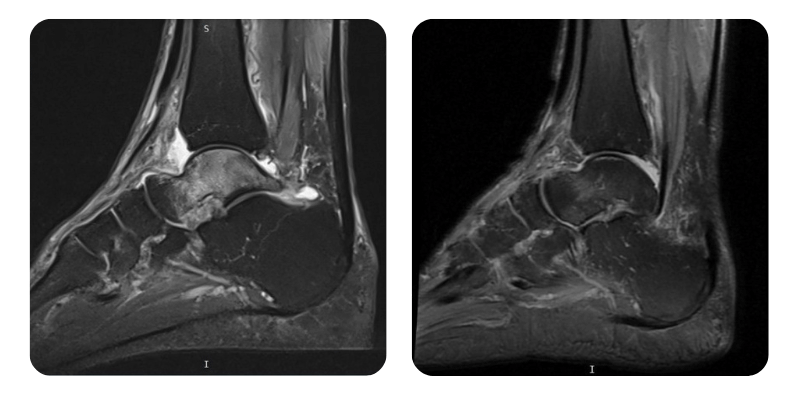

Vorher

Nachher

T.F., 68 Jahre – Avasculäre Nekrose des rechten Talus

Anamnese: Vor 3 Monaten erlitt der Patient eine Fraktur der distalen rechten Fibulaepiphyse, die mittels Gipsruhigstellung behandelt wurde. Einen Monat später kam es zu einer erneuten Verstauchung des Sprunggelenks, gefolgt von Schmerzen im Bereich des rechten Sprunggelenks. Die MRT-Untersuchung zeigte eine aseptische Nekrose des Talus. Bekannte Vorerkrankungen: arterielle Hypertonie unter Preductal-Therapie und Prostataadenom.

Ergebnisse: MRT des Fußes.

Diagnose: Avasculäre Nekrose des rechten Talus.

Verlauf: Das Ödem hat sich um etwa 90% zurückgebildet.